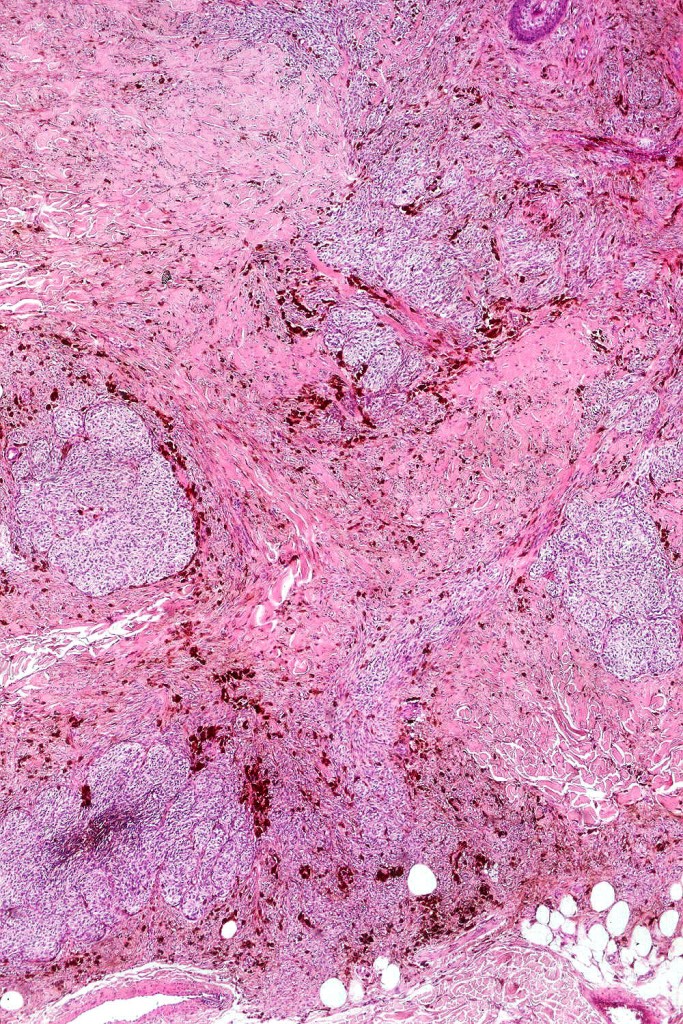

•Most characteristic is the dumbbell silhouette although a plague morphology may also be encountered

•Admixture of spindle cells, pigmented bipolar or dendritic cells & melanophages

•An alveolar pattern is characteristic particularly with clear cell nodules

•Multinucleate giant cells sometimes present

•Stromal fibrosis, myxoid change, vascular hyalinization with cyst formation are often seen